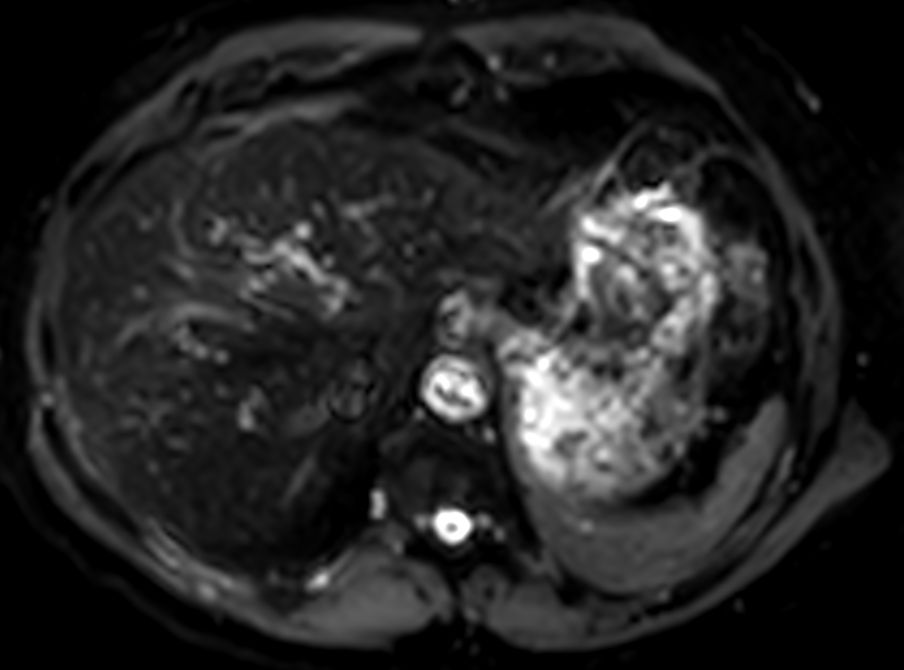

Liver imaging case, leveraging Philips SmartSpeed, our breakthrough new MRI application that delivers image and speed without compromise. Building on our proven technology and leveraging AI* to take fast MRI technology to the next level. Imaging speed is increased while providing greater resolution to deliver outstanding image quality. It covers motion imaging, free-breathing imaging and diffusion-weighted imaging to address the needs of a broad range of patients in various conditions.

Axial T2w TSE mDIXON (water only)SmartSpeed MotionFree